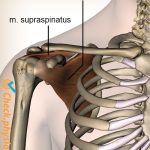

– Fascia quanh tim (pericardial fascia) kết nối với:

– Mạc ngực – cổ – cơ hoành

– Mạc vai – cổ qua cơ pericardial fascia

2/ Liên kết cơ – xương – khớp

a/ Xương liên quan:

– Cột sống ngực (T1–T5): Điều khiển thần kinh tim

– Xương ức – sườn: Bảo vệ tim

b/ Cơ liên quan:

– Cơ hoành (Diaphragma): Ảnh hưởng nhịp tim khi thở

– Cơ ức đòn chũm, liên sườn, cơ cổ trước: Căng thẳng có thể ảnh hưởng nhịp tim

(Hình ảnh đính kèm:)